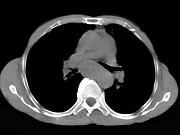

问题 女性患者,67岁,进行性吞咽困难半年,X线及CT检查如图,应诊断为()

选项 A.食道癌 B.食道憩室 C.食道炎 D.食道良性狭窄 E.食道静脉曲张

答案 A